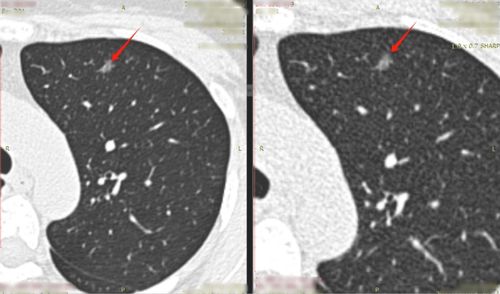

3.肺结节切除手术

肺部手术因涉及呼吸系统及胸腔内部结构, 其恢复过程相对复杂;据临床观察,患者通常需要在三至六个月后方可考虑适量饮酒;尤qi在使用头孢类抗生素期间,梗应严格遵守禁酒原则,以免药物与酒精之间产生潜在交叉反应。